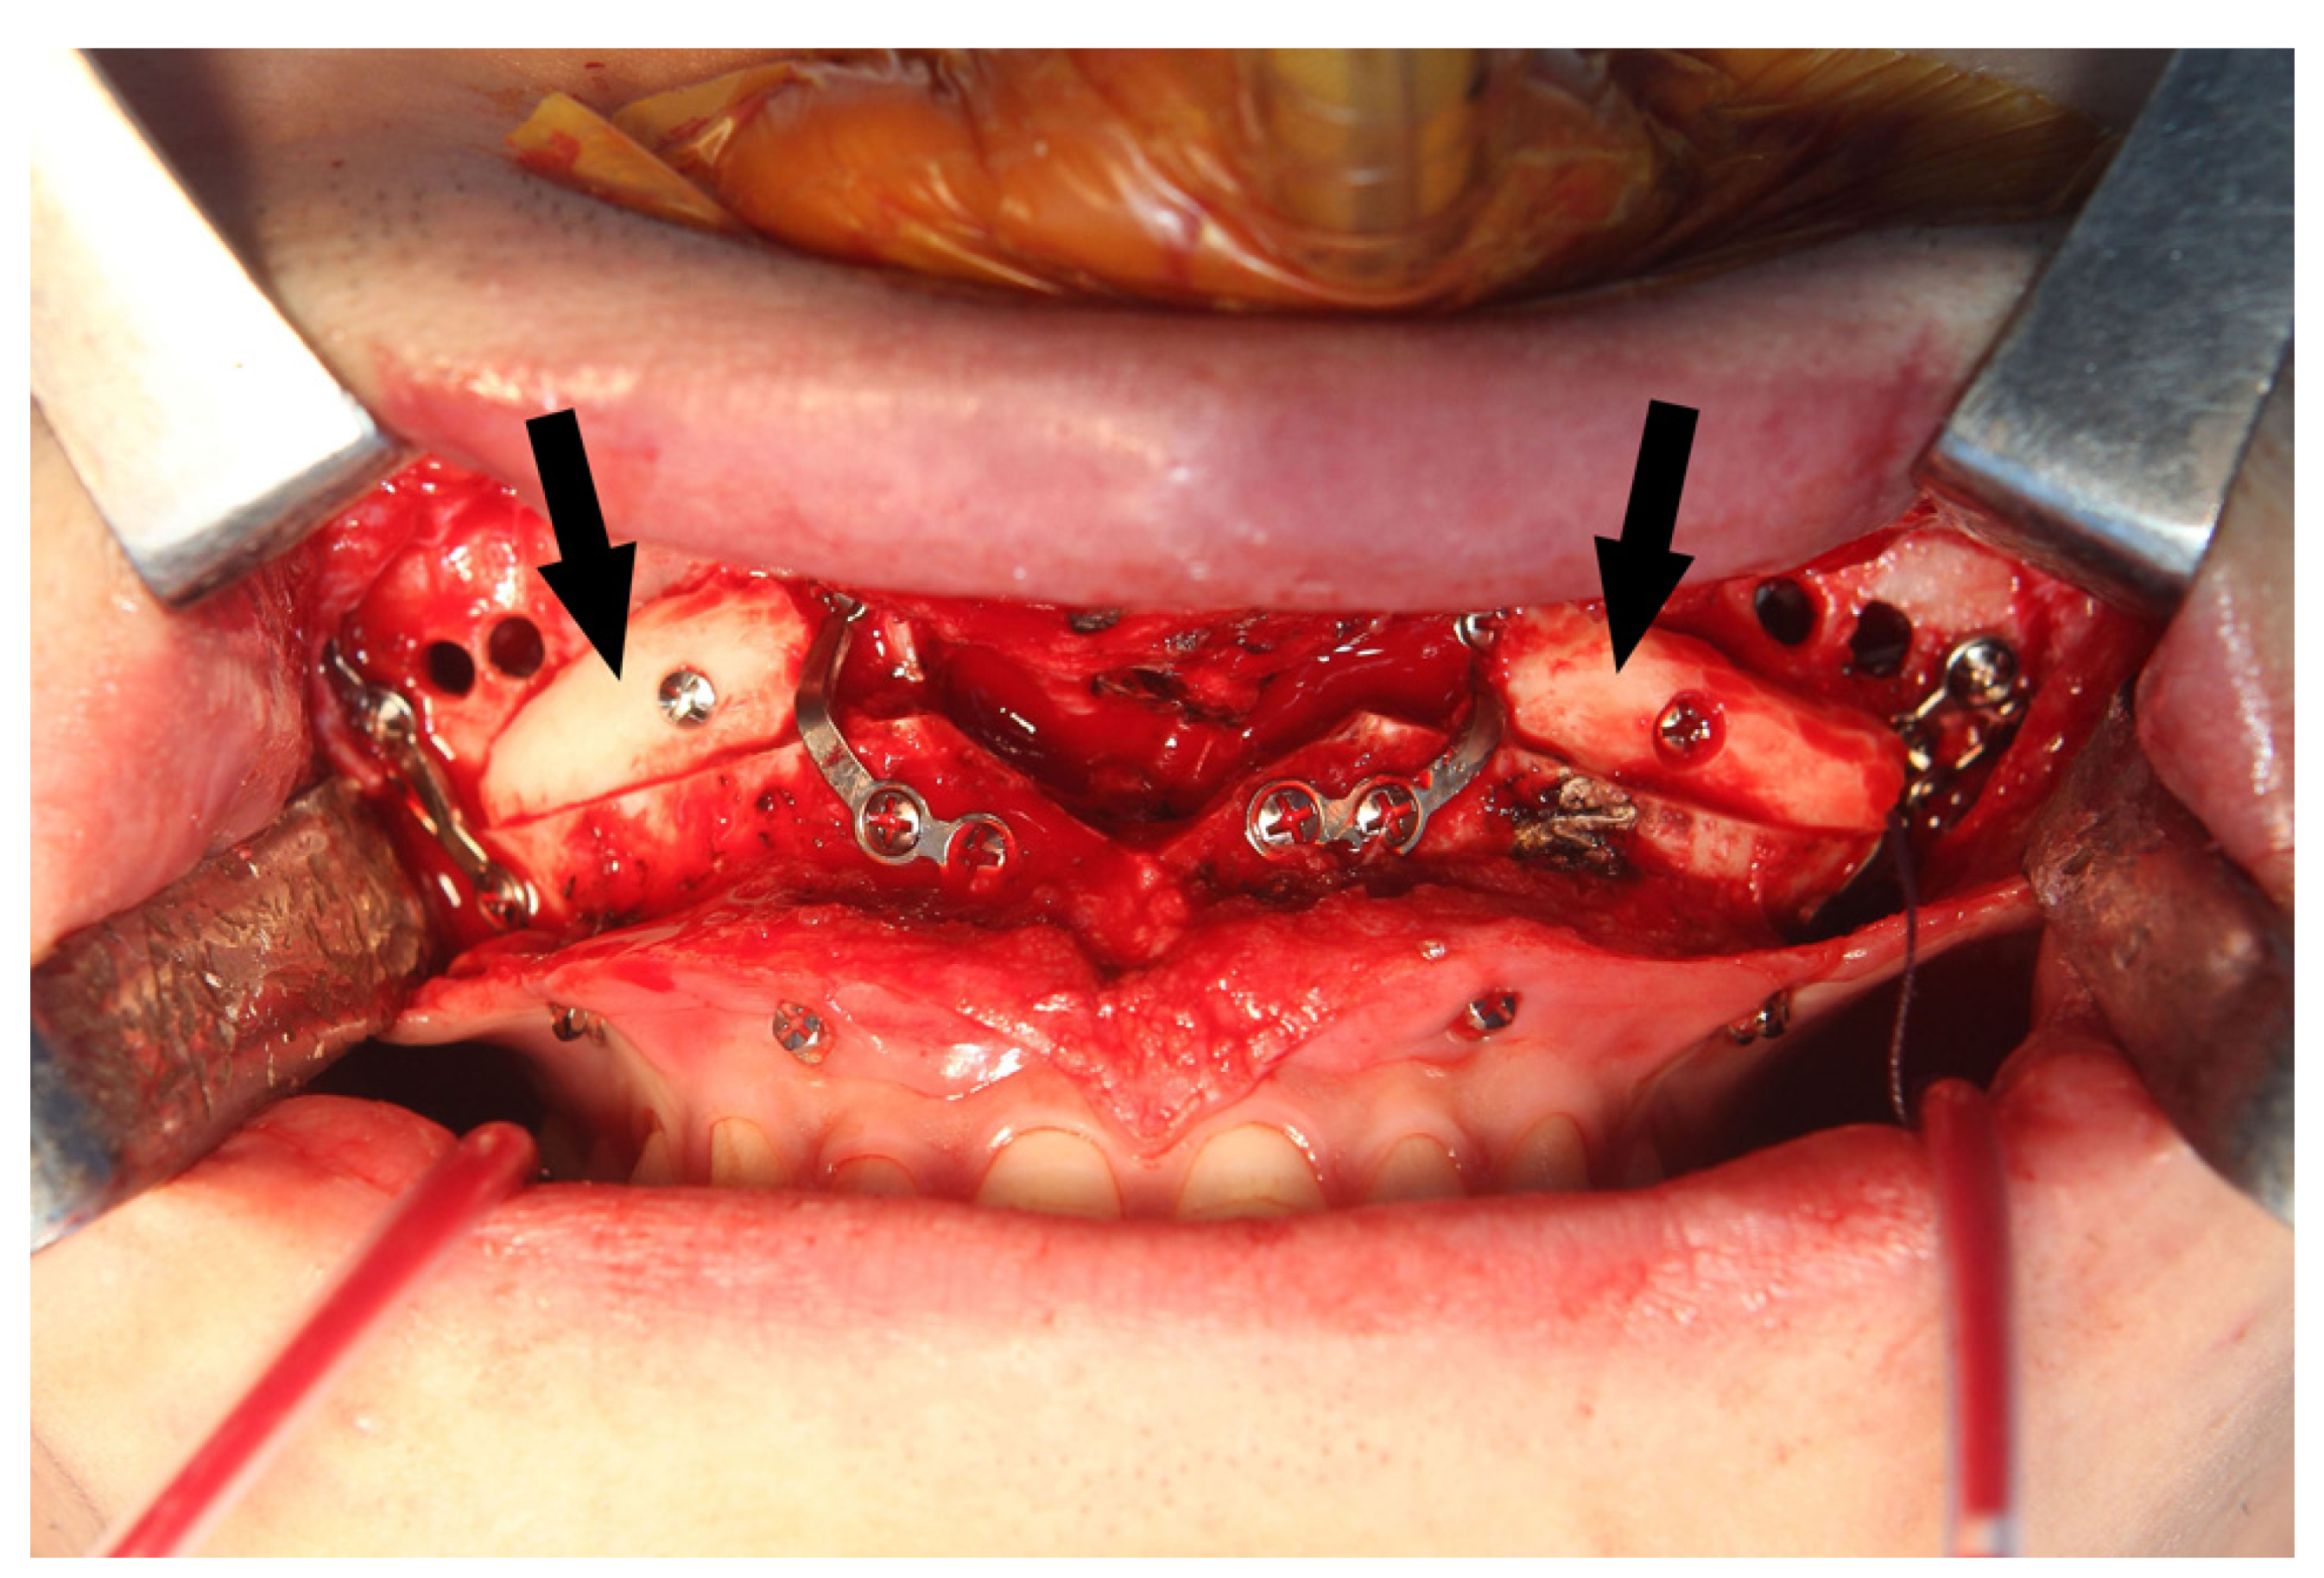

During the Le Fort I osteotomy, autogenous block bones were grafted at the bony gap of the anterior maxilla for postoperative stability of the maxilla and for achieving a more efficient drainage of the maxillary sinus by minimizing the communicating spaces (Figure 6).

Figure 6.

Autogenous block bone (arrows) was grafted at the bony gap of maxillary sinus wall for a more efficient drainage of maxillary sinus.

Questions may arise as to whether the bony holes drilled to apply the MSVD will heal completely with time. We observed that drilled bony holes had become smaller during the metal removal surgery at 2 years after bimaxillary orthognathic surgery (Figure 7). These remaining bony defects did not clinically affect the physiology or function of the maxillary sinus. At the last follow up, 4 years after the procedure, there were no other sino-nasal clinical symptoms or complications regarding the MSVD. All tubes should be removed the day after operation to prevent the active post-operative bleeding. According to our experience, there was no case of late bleeding in the group of patients with MSVD. However, it is important to alertly monitor for late bleeding.

Figure 7.

The drilled bony holes for the maxillary sinus ventilation drainage had become smaller (arrows) at 2 years after the bimaxillary orthognathic surgery.